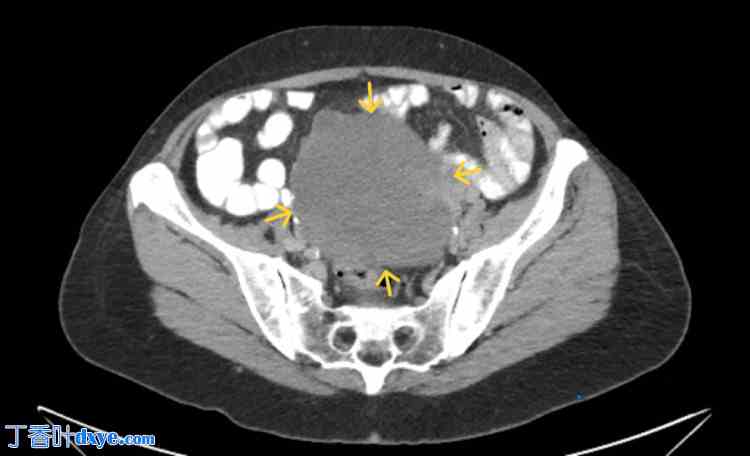

阴道检查时,发现一个大的无痛性盆腔肿块,位于道格拉斯陷凹内。经阴道超声检查显示一个边界清晰的回声肿块,包含实性和囊性成分,充满整个盆腔(图1)。

图1. 卵巢卵泡膜细胞瘤经阴道超声成像。

可见边界清晰的盆腔肿块(黄色箭头),主要为实性,并伴有少量囊性成分(红色箭头)。